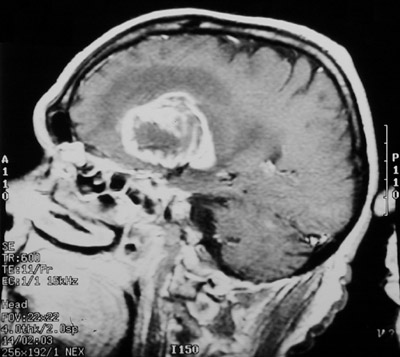

| This sagittal view MRI scan demonstrates a large glioblastoma multiforme of the right cerebral hemisphere with central lucency and an irregular, enhancing border. There is surrounding edema as well, which may be acute enough to produce signs of increased intracranial pressure, such as pappiledema, and even herniation. |